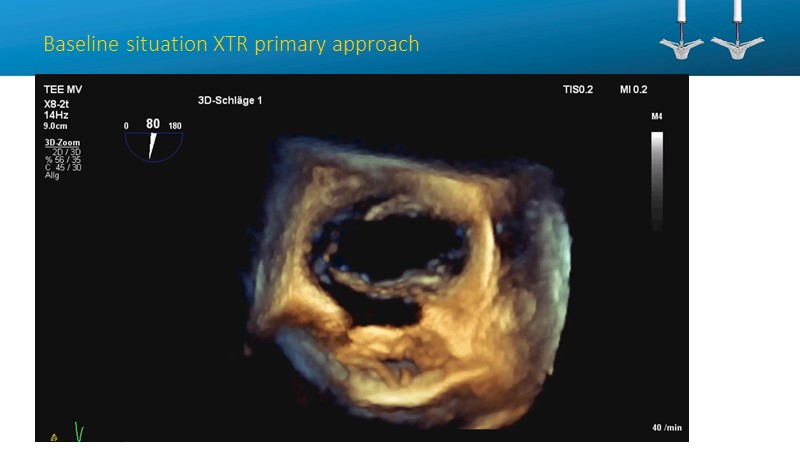

- To learn how will product innovation (Mitraclip NTR / XTR) drive improvement in procedural and clinical outcomes (EXPAND)